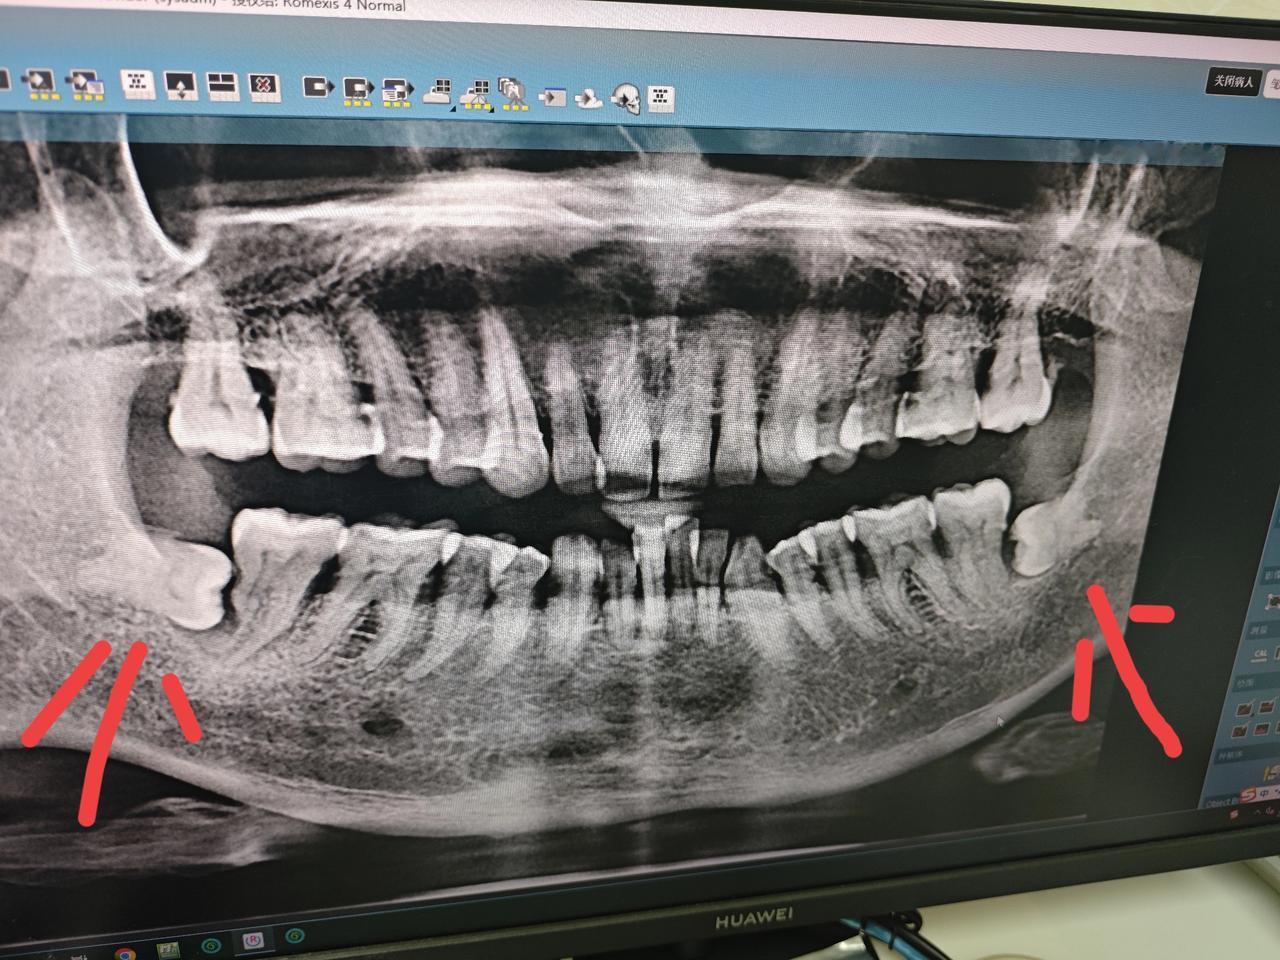

都说每个人有28颗牙齿,但是我却有30颗,还有的人有32颗。 最近因为牙齿痛,去医院照了一下, 才发现我自己也长了智齿。以前总听人家说智齿,但我却不知道智齿到底是个什么意思,长个什么样子。 这一次去检查,找出来才看到自己的智齿,原来是长这个样子。 28颗牙齿的人就是没有长智齿的人,像我这样30颗的就是下面或上面长了两颗,长32颗的就应该是上下都有,一边长了两颗。 都说智齿长出来就是为了要拔掉的,但我觉得应该他不痛就不用拔吧。 以前很多人都不知道有这事,那他们都没有拔,还不是就过来了。 最后我想问一下,我这个智齿怎么是横着长的?正不正常?智齿